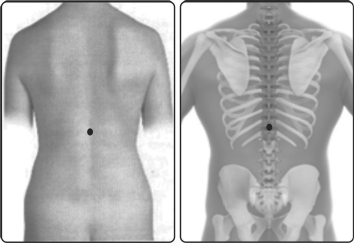

அல்லிவர்மம் நாபியின் நேர் பின்புறம் நான்குவிரலின் மேல் முதுகுத்தண்டில் அமைந்துள்ளது. இவ்வர்மம் அரசவர்மம், அல்லி அரச வர்மம், அல்லி அரசாணி வர்மம், சந்திர புஷ்கரணி வர்மம் என்னும் வேறுபெயர்களாலும் வழங்கப்படுகிறது.

அல்லிவர்மம் இரண்டு என்பார்கள். அது பெண்களுக்கு இருபுறமும் உள்ளுறக் காண்பதாம் ஒன்று. மற்றொன்று தண்டு எனப்படும் முதுகெலும்பில் நாபியின் பின்னிருந்து நான்கு விரல் மேலாக இருக்கும். அத்தலத்தில் தல்லலோ இடியோ மாத்திரை மிஞ்சிக் கொண்டிடில் உடலானது குழைந்துவிடும் என்பதாம்.